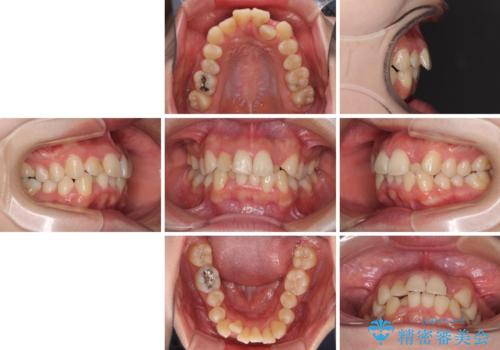

短期間で終了 デコボコをワイヤー矯正で解消

- 上下のデコボコと前歯のクロスバイトを改善したいとのことで来院された患者様です。

極力短期間で治療したいとのことで、ワイヤー装置による矯正治療を行うこととしました。

マウスピースによる矯正治療も提案しましたが、ご自身でのマウスピースの管理の面倒くささと、なるべく早く治療を終えたいとのことで、ワイヤー矯正を選択されました。